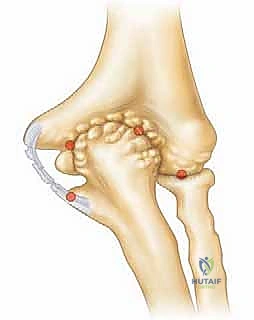

وبشكل محدد، يؤدي هذا الترهل إلى انحشار عظمي مباشر وعنيف بين الجانب الخلفي الإنسي من الناتئ المرفقي (Olecranon) والحفرة المقابلة له في عظم العضد (Olecranon Fossa). هذا الاحتكاك القوي والمتكرر هو أصل المرض، وهو ما يؤدي إلى تفتت الغضروف ونمو زوائد عظمية مؤلمة (Osteophytes) تعيق حركة فرد الكوع تماماً.

يمكن أن يؤدي الانحشار العظمي المزمن، كما هو الحال في متلازمة إجهاد الكوع الانقلابي، إلى إصابات غضروفية كبيرة – أي تلف وتآكل في الغضروف المفصلي الناعم الذي يغطي نهايات العظام – بالإضافة إلى تكوين نتوءات عظمية تفاعلية (Spurs) داخل الجزء الخلفي من المفصل.

وهذا هو السبب في أن سلامة الرباط الجانبي الزندي (UCL) أمر بالغ الأهمية. يتكون هذا الرباط من حزم أمامية وخلفية ومستعرضة، وتعتبر الحزمة الأمامية هي خط الدفاع الأول ضد قوى الانقلاب. عندما يضعف هذا الرباط، تفقد العظام مسارها الصحيح، ويبدأ الناتئ المرفقي (Olecranon) بالاصطدام بجدران الحفرة المرفقية، مما يخلق النتوءات العظمية التي تميز متلازمة إجهاد الكوع الانقلابي.

هذه هي الخطوة الأكثر دقة وحساسية، وهنا تتجلى خبرة الأستاذ الدكتور محمد هطيف. باستخدام أدوات دقيقة (Burr)، يقوم بنحت وإزالة النتوءات العظمية الخلفية التي تسبب الانحشار.

تحذير جراحي هام: يؤكد الدكتور هطيف دائماً على قاعدة جراحية ذهبية في هذه العملية: "يجب إزالة العظام الزائدة فقط (النتوءات)، ويجب عدم المبالغة في إزالة جزء من العظم الأصلي للناتئ المرفقي". لماذا؟ لأن الإفراط في إزالة العظم سيؤدي إلى فقدان المفصل لاستقراره العظمي، مما يضع ضغطاً مضاعفاً ومميتاً على الرباط الجانبي الزندي (UCL)، وقد يؤدي إلى تمزقه بالكامل لاحقاً. هذه الدقة في تحديد "كمية العظم المزال" هي ما يميز الجراح الخبير عن غيره.